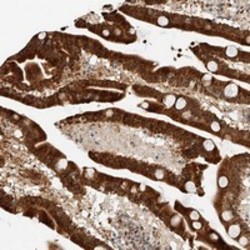

- Immunohistochemical staining of human duodenum with ATXN7L2 polyclonal antibody (Cat # PAB22352) shows cytoplasmic and nuclear positivity in glandular cells at 1:200-1:500 dilution.

- Immunohistochemistry (Formalin/PFA-fixed paraffin-embedded sections)